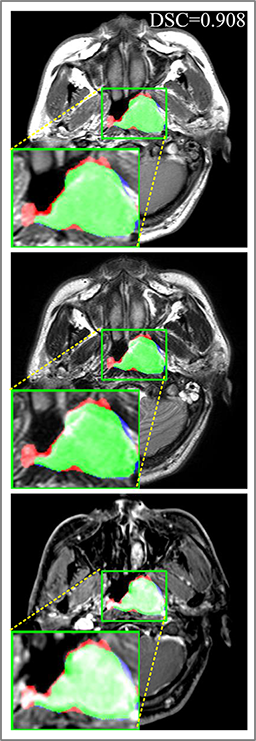

Refer to caption

(a) DSC=0.915

(b) DSC=0.870

(c) DSC=0.902

(d) DSC=0.898

Figure 7: Predicted results of proposed MMFNet in 2D images. There are corresponding T1, T2 and CET1 images from top to down. Boundaries created by radiologists are marked in red line, and the predicted boundaries are shown in blue line. The DSC𝐷𝑆𝐶DSC value is the dice similarity coefficient of this single slice.

Figure 9: Predicted results in one single slice image, there are corresponding T1, T2 and CET1 images from top to down. Green regions denote TP𝑇𝑃TP points, red and blue regions denote FP𝐹𝑃FP and FN𝐹𝑁FN point. (a) Ground truth. (b) Patch-based CNN (CET1). (c) Multi-modality patch-based CNN. (d) U-net (CET1). (e) 3D U-net (CET1). (f) Input-level fusion. (g) Merging encoders’ features. (h) MMFNet + multi-MLP + stdPool + self-transfer.

Comparison with ground truth. Some predicted results of MMFNet are shown in 2D images and 3D images in Figure 7 and Figure 8. As shown in these figures, although the shape and size of NPC are varied from each other, MMFNet can still accurately determine the regions of NPC and obtain the accurate contours of tumors. Through analyzing 2D images in figure 7, MMFNet has a capacity to fuse multi-modality MRI to reduce the confusion brought by intensity’ similarity between nearby tissues and NPC. The values of meanDSC𝑚𝑒𝑎𝑛𝐷𝑆𝐶meanDSC, meanASD𝑚𝑒𝑎𝑛𝐴𝑆𝐷meanASD and meanHD𝑚𝑒𝑎𝑛𝐻𝐷meanHD of MMFNet are shown in Table 1. MMFNet can reach the best results with DSC=72.38%,meanASD=2.07mmformulae-sequence𝐷𝑆𝐶percent72.38𝑚𝑒𝑎𝑛𝐴𝑆𝐷2.07𝑚𝑚DSC=72.38\%,meanASD=2.07mm, and meanHD=18.31mm𝑚𝑒𝑎𝑛𝐻𝐷18.31𝑚𝑚meanHD=18.31mm.

Comparison with related works. Table 1 reports the values of meanDSC𝑚𝑒𝑎𝑛𝐷𝑆𝐶meanDSC, meanASD𝑚𝑒𝑎𝑛𝐴𝑆𝐷meanASD and meanHD𝑚𝑒𝑎𝑛𝐻𝐷meanHD for different methods. Predicted masks of different methods are illustrated in Figure 9 and Figure 10, which respectively present results in 2D and 3D images. Through comprehensively analyzing these results, the proposed MMFNet actually have the following properties: